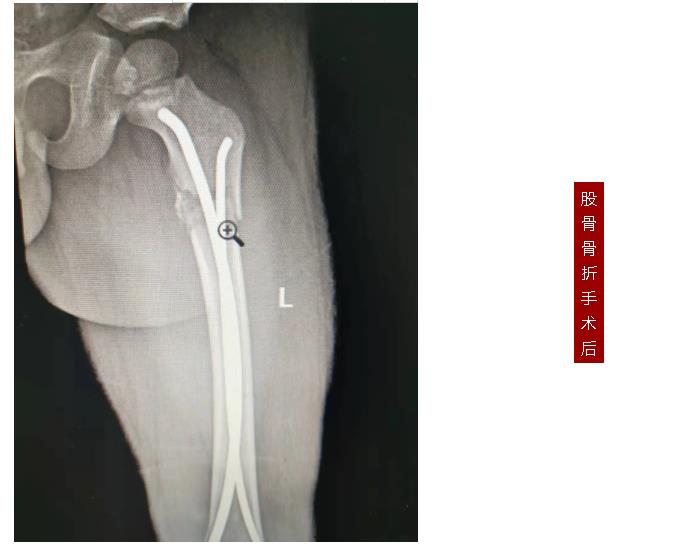

887700线路检测网骨伤二科副主任张永青仔细查看孩子患处,安排其进行放射拍片检查,结果为左侧桡骨颈骨折,根据孩子的骨折状况,张主任认为保守治疗很难做到理想复位,且复位后较难维持良好位置,可能会影响将来前臂的旋转功能,建议孩子尽快接受手术治疗,孩子的家长担心传统手术切口大,孩子所受痛苦多,犹豫不决,张主任与家长沟通,孩子要接受的不是传统的开放手术,而是“骨折闭合复位弹性髓内钉内固定”微创手术,手术只需要一个0.5-1厘米左右的切口就可以达到满意的效果,家长立即同意接受手术治疗。手术非常成功,术后第三天,周周出院。

张永青介绍,“弹性髓内钉技术”是儿童骨科界的一次革命,被誉为上帝赐予长骨骨折儿童的礼物,该项技术可在保护骺板不受损伤的前提下,利用多点固定的原理,微创、有效地治疗4-12岁的四肢骨折患儿,该技术利用钛合金或不锈钢良好的弹性、恢复力将作用于长骨的3个接触点转换成推力和压力,从而使骨折复位,有足够的力量抵抗骨折端移位作用,该方法不需要剥离骨膜和切开骨折端,不干扰骨骺生长,也不破坏骨折端血运,弹性固定、局部微动、创伤小、骨折愈合快,术后3周即可进行功能锻炼,术后1个月功能恢复正常。

887700线路检测网骨伤科自2018年在我市率先开展弹性髓内钉技术至今,共收治20多例四肢长骨骨折患儿,手术均为闭合复位或小切口辅助复位,在40分钟内完成,创伤小,恢复快,术后3-5天即可出院,大大减少了治疗费用和住院时间,减少了患儿的痛苦。